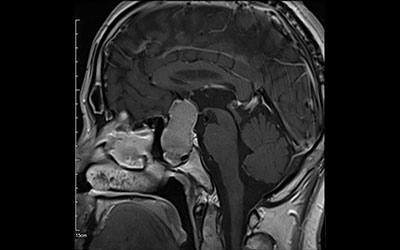

鼻の孔から内視鏡を挿入し脳腫瘍の摘出を行なう手術です。最新最高性能のメドトロニック社製磁場式ナビゲーションシステムを用いて、顔、口腔内、頭皮を傷つけることなく脳内の手術を実施しています。

手術前